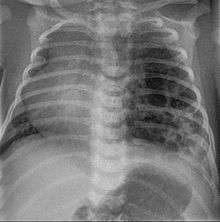

CPAMs are often identified during routine prenatal ultrasonography. Identifying characteristics on the sonogram include: an echogenic (bright) mass appearing in the chest of the fetus, displacement of the heart from its normal position, a flat or everted (pushed downward) diaphragm, or the absence of visible lung tissue.

Imaging

The earliest point at which a CPAM can be detected is by prenatal ultrasound. The classic description is of an echogenic lung mass that gradually disappears over subsequent ultrasounds. The disappearance is due to the malformation becoming filled with fluid over the course of the gestation, allowing the ultrasound waves to penetrate it more easily and rendering it invisible on sonographic imaging. When a CPAM is rapidly growing, either solid or with a dominant cyst, they have a higher incidence of developing venous outflow obstruction, cardiac failure and ultimately hydrops fetalis. If hydrops is not present, the fetus has a 95% chance of survival. When hydrops is present, risk of fetal demise is much greater without in utero surgery to correct the pathophysiology. The greatest period of growth is during the end of the second trimester, between 20–26 weeks.